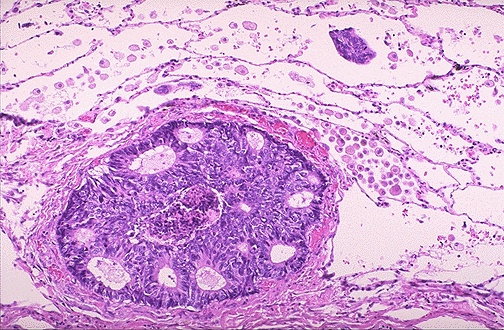

Both lymphatic and hematogenous spread of malignant neoplasms is possible to distant sites. Here, a breast carcinoma has spread to a lymphatic within the lung.